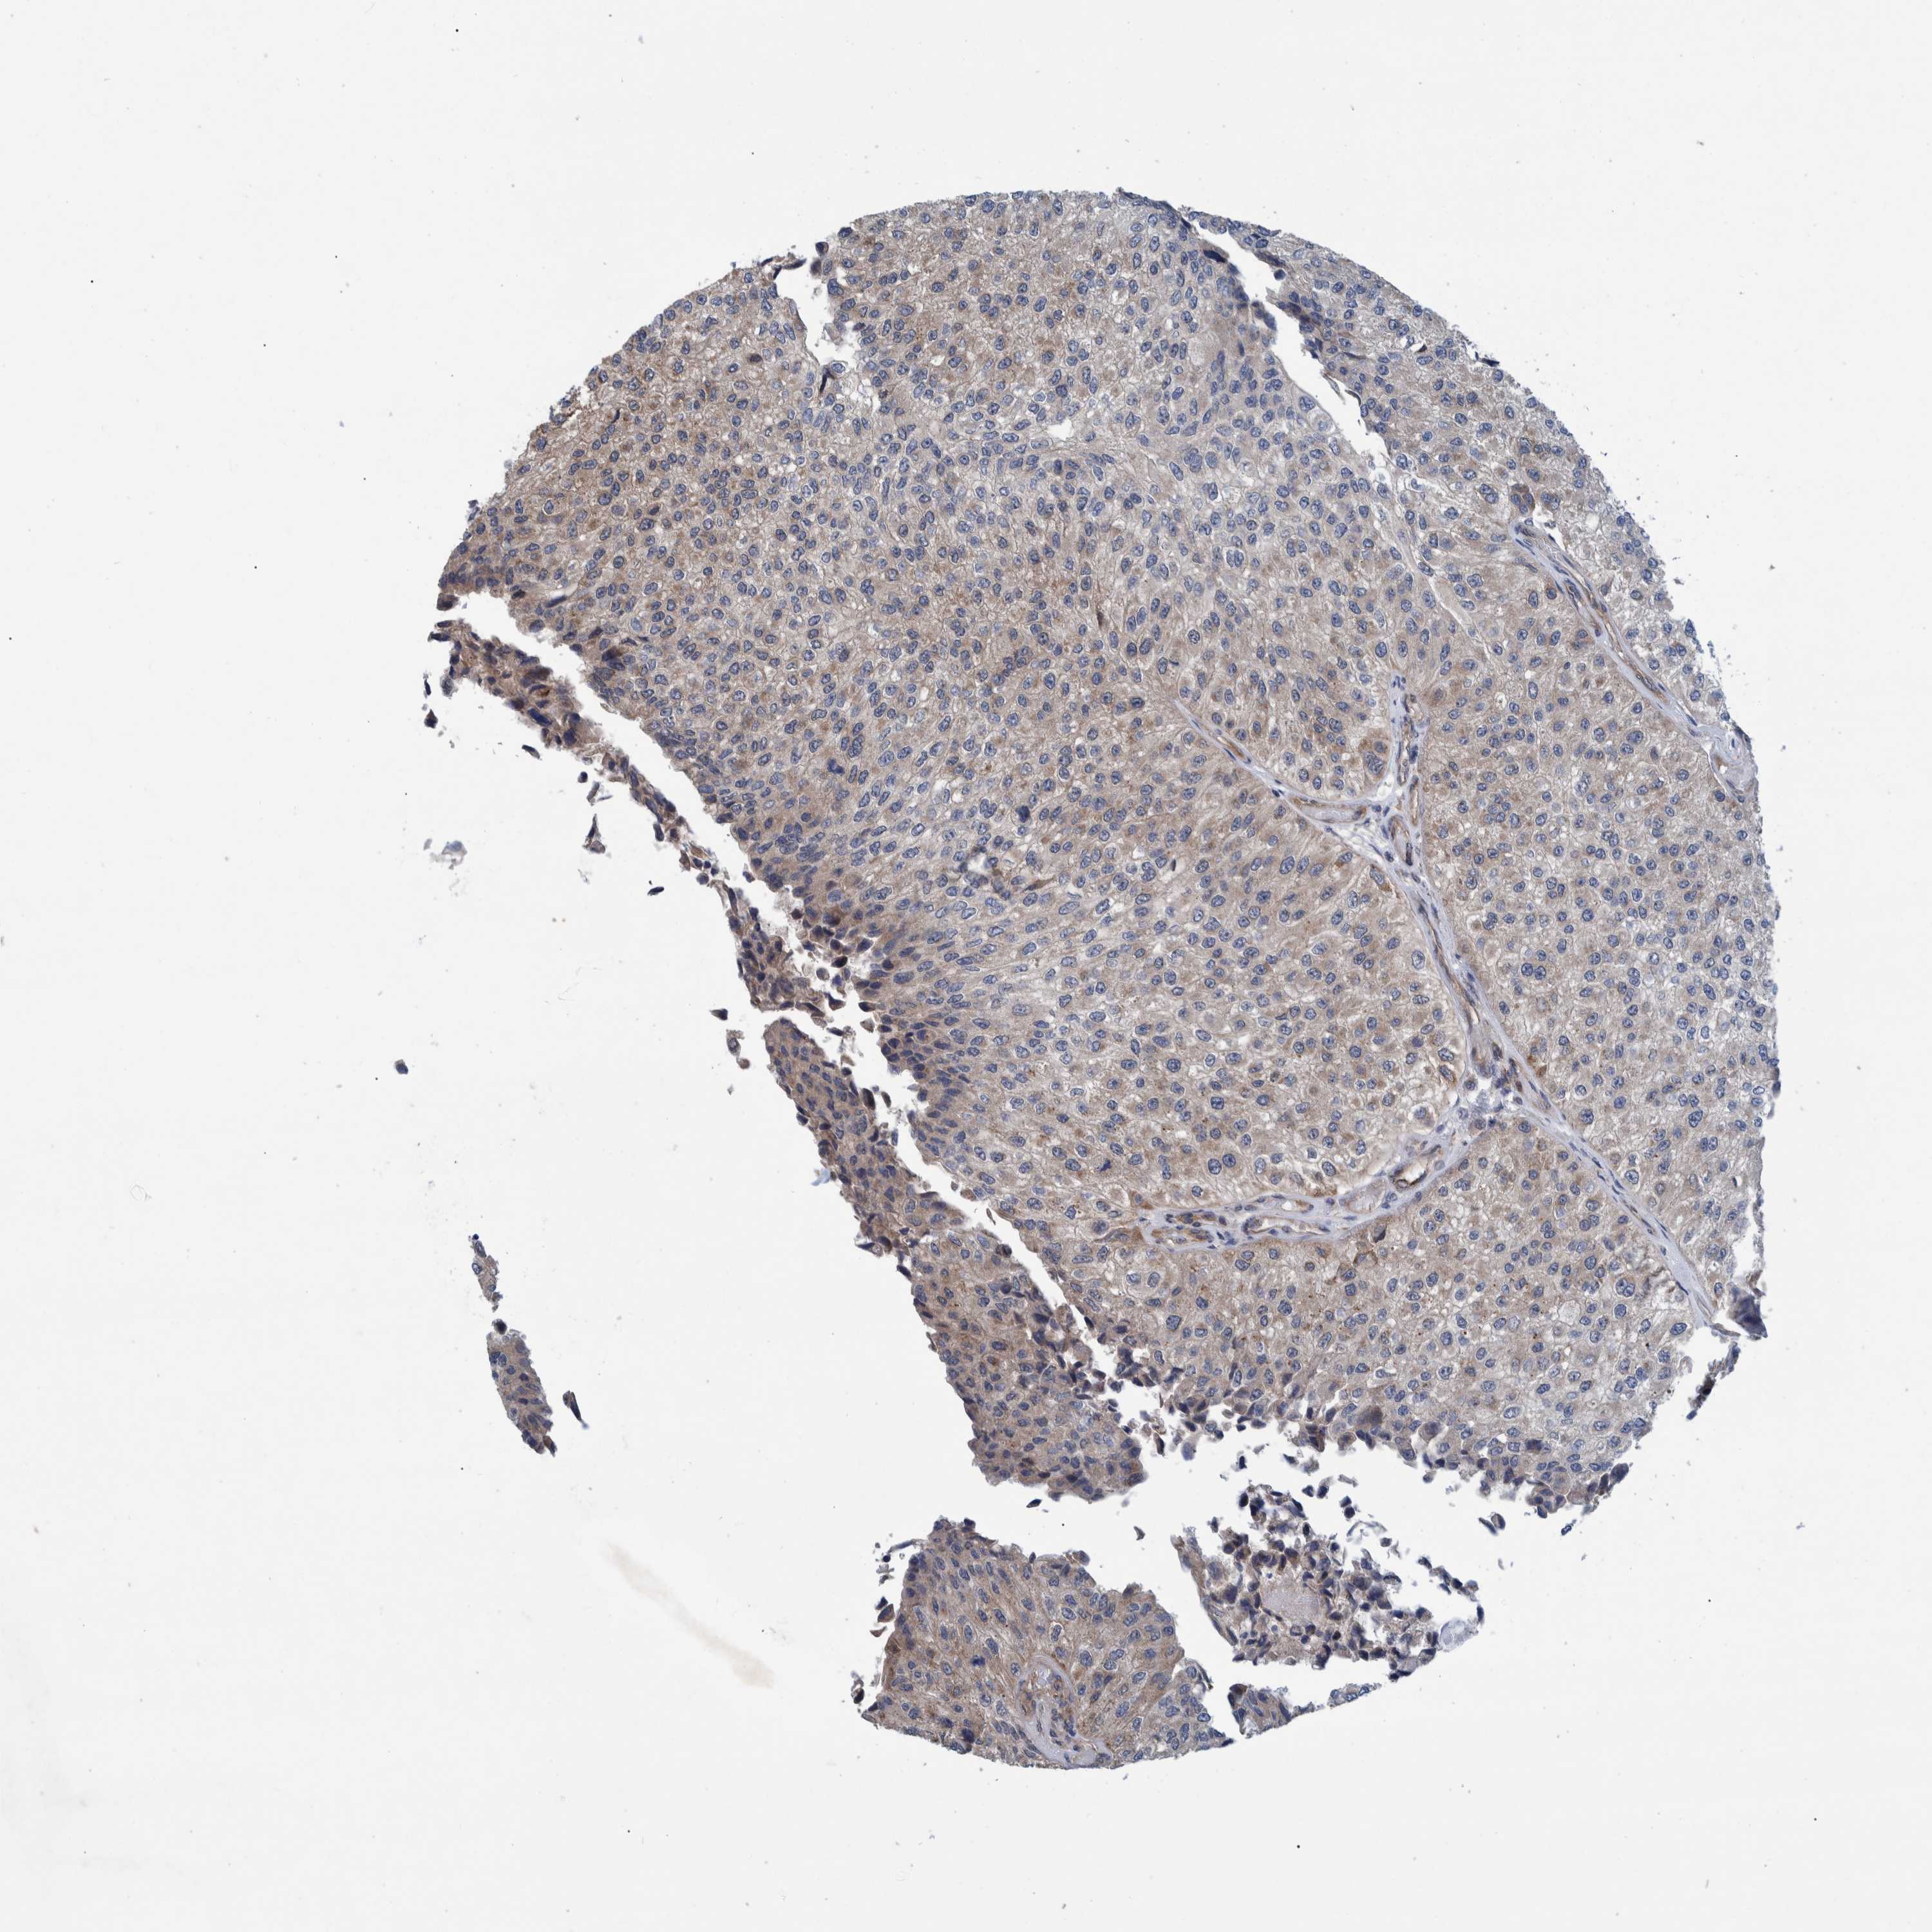

UROTHELIAL CANCER - Protein expressioni

A mouse-over function shows sample information and annotation data. Click on an image to view it in a full screen mode. Samples can be filtered based on level of antibody staining by selecting one or several of the following categories: high, medium, low and not detected. The assay and annotation is described here.

Note that samples used for immunohistochemistry by the Human Protein Atlas do not correspond to samples in the TCGA dataset.

Antibody stainingi

Antibody staining in the annotated cell types in the current human tissue is reported as not detected, low, medium, or high, based on conventional immunohistochemistry profiling in selected tissues. This score is based on the combination of the staining intensity and fraction of stained cells.

Each image is clickable and will lead to virtual microscopy that enables deeper exploration of all samples and also displays staining intensity scores, fraction scores and subcellular localization as well as patient and tissue information for each sample.

Antibody HPA022522

Urothelial carcinoma, Low grade

Urothelial carcinoma, High grade